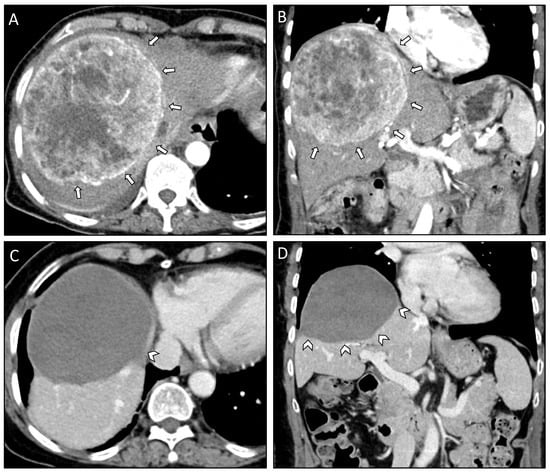

| Case Number | #1 | #2 | #3 |

|---|---|---|---|

| Patient age at diagnosis (years) | 67 | 39 | 65 |

| Patient sex | Female | Female | Female |

| Comorbidities/Notes | Parkinson’s disease | Childbed | Depression |

| WHO grade | II | II | II |

| Mitosis/10 HPF | 0 | 2 | 2 |

| Ki-67 index | 5% | 10–15% | 2% |

| Liver metastasis | |||

| Time to occurrence from initial diagnosis (years) | 8 | 8 | 15 |

| Location at initial diagnosis | Right lobe | Bilobar | Bilobar |

| Number at initial diagnosis | 1 | 3 | 3 |

| Size of largest metastasis at initial diagnosis | 13 cm | 12 cm | 13 cm |

| Paraneoplastic syndromes | Hypercalcemia | Hypoglycemia | None |